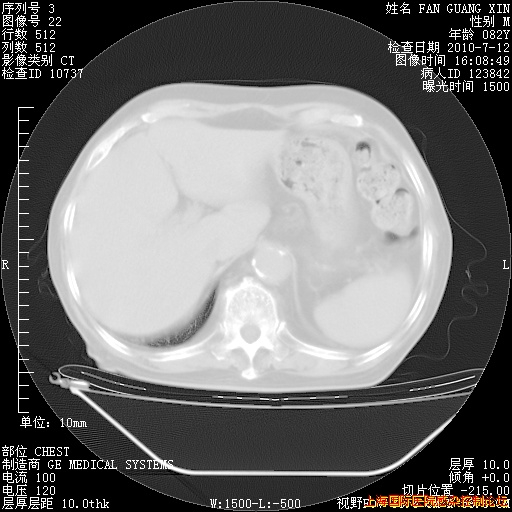

今天复查CT

回复

整整相隔30天的肺部CT好像有所好转啊。甲强龙减量第3天,需要观察体温。